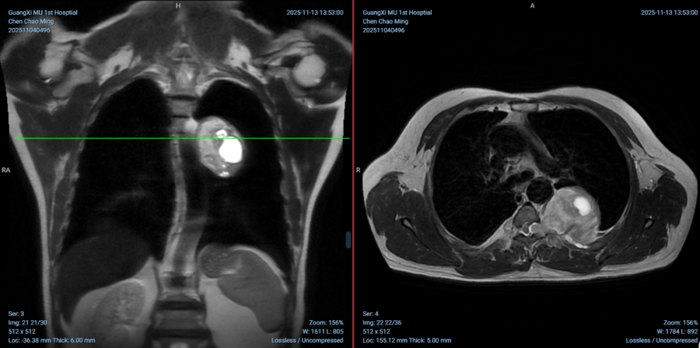

▲术前影像可见巨大的神经鞘瘤且与胸椎椎管相通。

患者肿瘤位置极为特殊,瘤体跨越脊柱椎间孔,一部分位于椎管内,另一部分则通过椎间孔突入左后纵膈,紧贴胸主动脉及交感神经链生长。此类肿瘤血供丰富,解剖关系复杂,传统手术方式面临巨大挑战:

面对这一难题,脊柱骨病外科与胸外科的多学科专家会诊。经过深入的术前讨论和基于CT、MRI影像的精确解读,团队最终决定打破常规手术思维,设计了一套“前后夹击”式联合微创手术方案:后路AUSS技术进行胸椎内的切除与向前推送,前面行胸腔镜手术进行整个肿瘤的切除及取出。